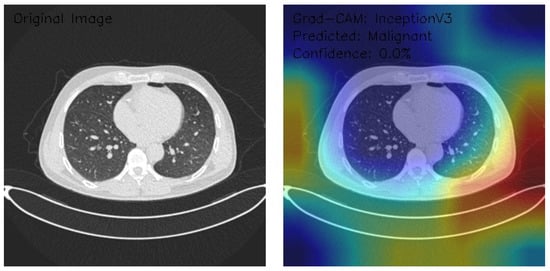

Analysis of InceptionV3 Model Performance on Lung CT Images with Grad-CAM Visualization

The results section of this study presents the detailed findings from an advanced analysis of three axial chest CT images processed using the InceptionV3 deep learning model. This analysis leverages the sophisticated capabilities of Grad-CAM to provide a comprehensive visualization of the regions within the CT images that the model identifies as significant for its predictions. Combining the robust classification performance of the InceptionV3 architecture with the interpretability offered by Grad-CAM, this approach not only evaluates the model’s predictive accuracy but also elucidates the spatial patterns of attention within the medical imaging context. This dual focus allows for a deeper understanding of the diagnostic potential of deep learning in radiology and the interpretive transparency essential for clinical application. The following results detail these observations, highlighting key insights into the model’s behavior and implications for automated diagnostic processes.

Figure 10 shows that the CT image analysis highlights scattered nodular opacities, suggesting potential abnormalities. The Grad-CAM visualization indicates peripheral activation patterns, with a notable focus on lateral lung regions. The heatmap’s color gradients suggest varying feature importance across these areas. Despite identifying relevant features, the model classifies the image as Malignant with a confidence score of 0.0%, reflecting significant uncertainty. This indicates a disconnect between the model’s feature detection and its confidence in classification, emphasizing the need for recalibration and potential retraining to enhance diagnostic reliability and decision-making accuracy.

Figure 10.

This analysis evaluates three axial chest CT images processed by an InceptionV3 model with Grad-CAM visualizations, focusing on attention regions and classification outcomes. Image 1 shows clear lung fields with symmetric central activation, classified as Normal with 0.0% confidence. Image 2, with scattered nodular opacities, displays peripheral activation patterns and is classified as Malignant, again with 0.0% confidence. Image 3 exhibits interstitial patterns with strong central and right-sided activation, also classified as Normal with 0.0% confidence. The Grad-CAM visualizations highlight relevant anatomical features, but the model’s uniform low confidence scores reveal calibration and classification inefficiencies. Recommendations include the recalibration of confidence scoring, fine-tuning classification layers, and integrating ensemble methods. While feature detection appears robust, these refinements are critical for clinical reliability and decision-making.